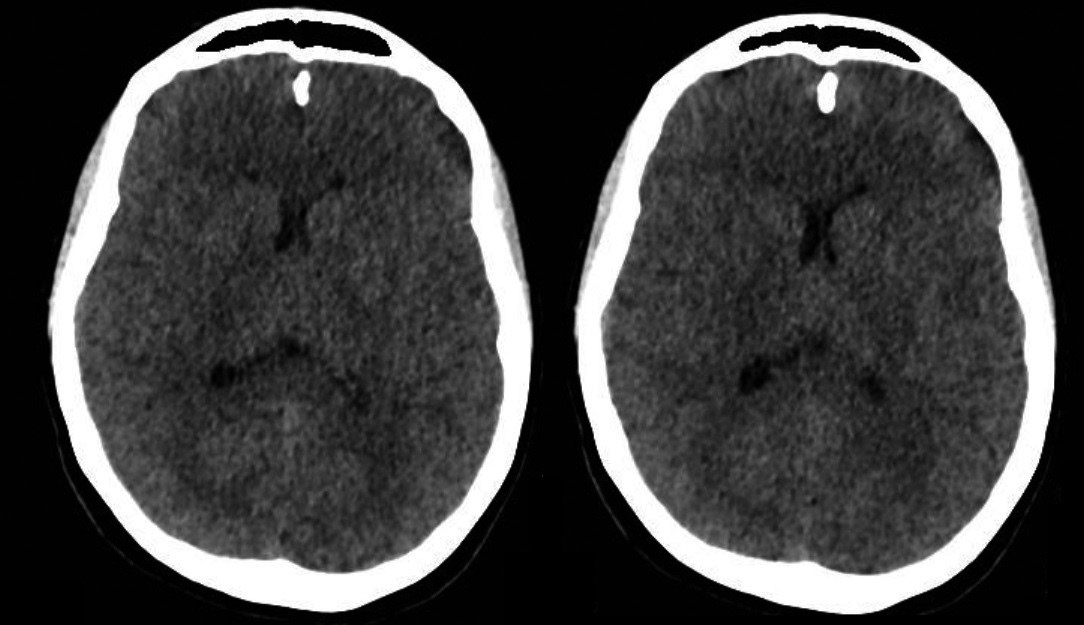

Los estudios de extensión no dan evidencia de alteración metabólica ni de infección intercurrente, una tomografía computarizada (TC) cerebral sin contraste no demuestra alteraciones (figura 1). Se realiza un video electroencefalograma de tres horas que demuestra trazado compatible con encefalopatía leve, sin evidencia de actividad irritativa focal. Se decide profundizar con una resonancia magnética cerebral en búsqueda de otros diferenciales; dicho estudio que se realiza 72 horas posteriores a la tomografía inicial, evidencia lesión isquémica subaguda bilateral en los globos pálidos (figura 2). En los días siguientes la paciente presenta empeoramiento de los síntomas ansiosos y afectivos, manifestando marcada inquietud motora e incapacidad para permanecer quieta, sugestivo de un cuadro de acatisia, el cual se modula con aumento de la dosis de antipsicótico y suspensión del antidepresivo. Progresivamente hay control de los síntomas, mejoría del afecto, regulación del ciclo sueño-vigila, sin presentar nuevas alteraciones de la sensopercepción ni ideas delirantes. Además, y llamativamente, el dolor crónico y la necesidad de consumo de opioides remiten completamente, permitiendo rápidamente el desmonte de la metadona, previamente iniciada para el manejo del TUS. Luego de aproximadamente tres semanas de tratamiento intrahospitalario, la paciente es dada de alta para continuar seguimiento por psiquiatría y toxicología de forma ambulatoria.